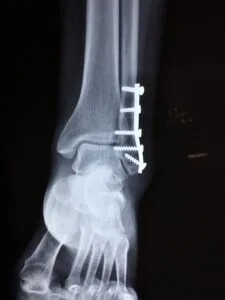

An ankle sprain can be characterized by lateral ankle pain, swelling, and instability. A stress X-ray may be useful in diagnosing fractures.